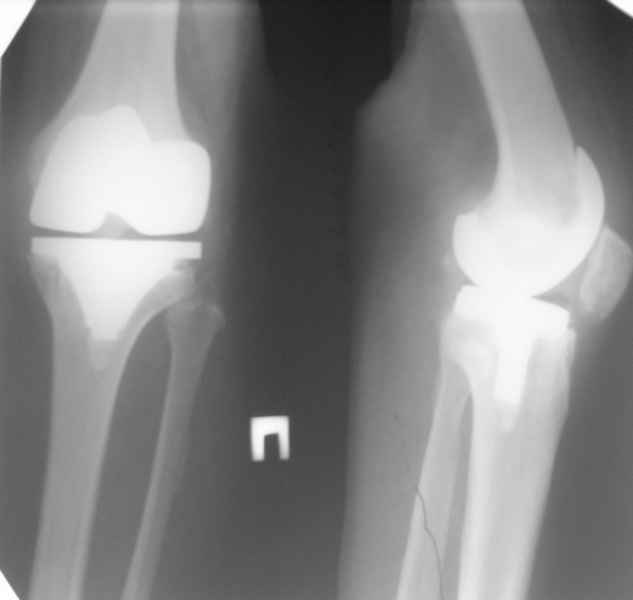

13/02/07 |  25/07/07 |  дек. 07 |  25/06/08 |  14/01/09 | Через 1 месяц после операции объем движений 90 градусов, через 2 месяца 60, через 3 - 40, через 5 - качательные движения.

Ты мне говорил об этом случае, а теперь я увидел снимки. Для исключения или подтверждения гнойного процесса надо взять обязательно посев. По-моему и бедро шатается. Ревизовать при ислючении гнойно-септических осложнений надо полностью либо CCK комплектом или связанным.

Учитывая, что в Вашем случае, кроме артрофиброза, несостоятельность протеза, я бы рекомендовал двухэтапную операцию.

Сперва артротомия с разработкой и установка антибиотического спейсера, затем артропластика по вашему усмотрению. CPM continuous passive motion с первых дней.